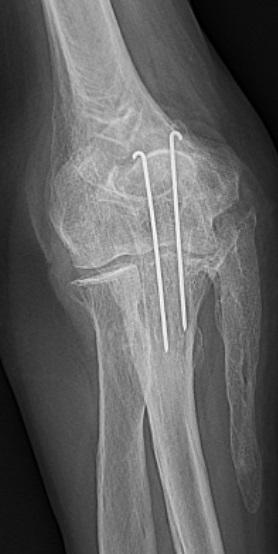

Röntgenfoto van de elleboog

Een 77-jarige man had 15 jaar geleden een olecranonfractuur gehad. Nu heeft hij geringe pijn in zijn rechter elleboog. Aan de ulnaire zijde van de onderarm zit een harde zwelling. Er wordt een röntgenfoto van de elleboog gemaakt.